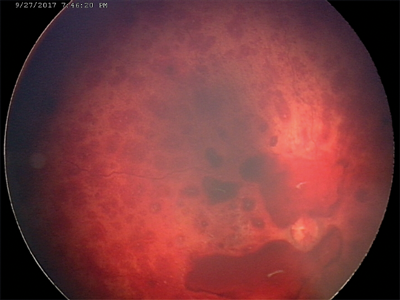

Figure 3: RetCam images of child with suspected non-accidental injury

with bilateral multi-layered retinal haemorraghes.

Advances in digital fundal imaging in children have transformed diagnosis and monitoring of a wide range of children’s eye diseases. RetCam and newer more portable digital fundal imaging devices (such as PanoCam) are now routinely used in infants and young children for the documentation of retinal disease (Figure 2). Digital imaging is particularly important for the diagnosis, monitoring and documentation of retinopathy of prematurity (ROP) [2]. It has significantly enabled trained non-medical users to send images obtained in the neonatal intensive care unit (NICU) to a remote expert for interpretation - true ‘telemedicine’. This principle may be transformative for the delivery of high quality ROP care in the developing world where paediatric ophthalmologists are scarce. Digital documentation of retinal haemorrhages in cases of suspected non-accidental injury is important both clinically and from a medico-legal aspect (Figure 3).

The images obtained are important evidence for subsequent hearings in both the family and criminal courts. Optos widescreen digital imaging can be carried out from at least four years of age in a cooperative child and provides quickly captured wide angle images (Figure 4). These are excellent for assisting the clinician in diagnosis and monitoring of both paediatric retinal disease, retinoblastoma and posterior uveitis. Fluorescein angiography and the autofluorescence functions of digital imaging systems have similarly assisted accurate diagnosis and delineation of maculopathy, retinal ischaemia and subretinal neovascular membranes in paediatric retinal disease.